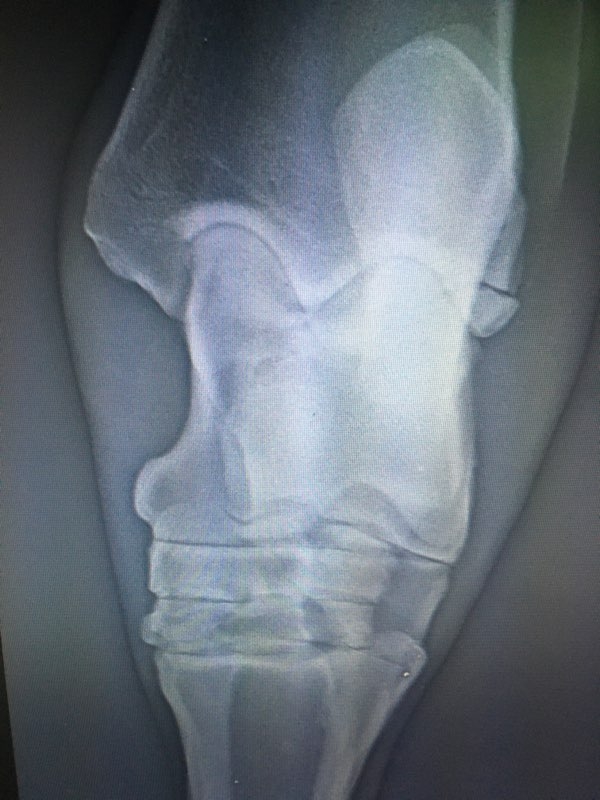

| Dire merci | Bonsoir à tous, Je ne poste pas pour moi mais pour une amie dont le cheval a lourdement chuté au pré et s'est fait une fracture de la malléole à chaque postérieur... Plusieurs vétérinaires ont vu le cas, le cheval est debout, marche trotte parfois mais a quand même mal évidemment... Quelqu'un a déjà eu le cas ? Quel suivi a été mis en place ? Opération ? Convalescence ? Si convalescence quel protocole ? Car les avis divergent sur la gestion du cas. J'ai les radios que je mets en spolier. Merci à tous ![]() Clichés : |

| Dire merci | La vache il s'est claqué les jambes en tombant comme un sac sur le côté ?! ![]() Dans l'immédiat, c'est ni comminutif, ni intra articulaire, ni déplacé, et sur une faible surface. Donc " Positif" Jamais eu le cas . Je dirais immobilisation stricte au box si le cheval tient le box durant quelques semaines (4 a 6) puis radio de contrôle et petit paddock avec des protections type trotteur avec un bon bilan loco a la clef. Et vu le placement et le risque ligamentaire, attention au sol et au parage si le cheval reprend le boulot. Mais encore une fois, jamais eu le cas donc... |